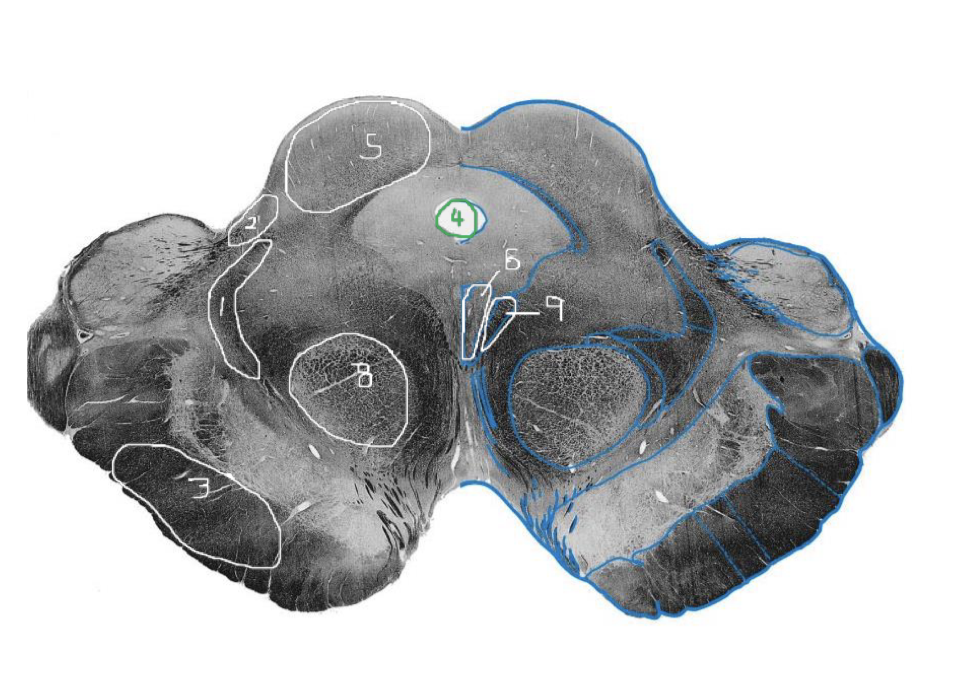

1

Medial Lemniscus - Rostral Midbrain

2

Spinothalamic Tract - Rostral Midbrain

3

CST - Rostral Midbrain

4

Cerebral Aqueduct - Rostral Midbrain

5

Superior Colliculus - Rostral Midbrain

6

Oculomotor Nucleus (CN III) - Rostral Midbrain

7

Interpeduncular Fossa - Rostral Midbrain

8

Red Nucleus - Rostral Midbrain

9

Medial Longitudinal Fasciculus (MLF) End Site - Rostral Midbrain